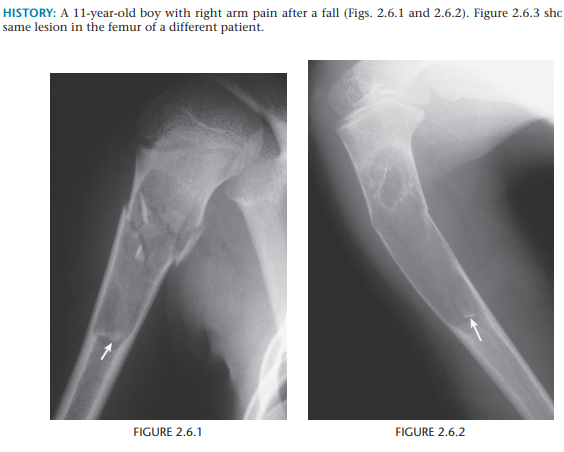

Unicameral bone cyst

Unicameral bone cysts are most common in the proximal humerus and femur.

The fallen-fragment sign confirms the cystic nature of this lesion.